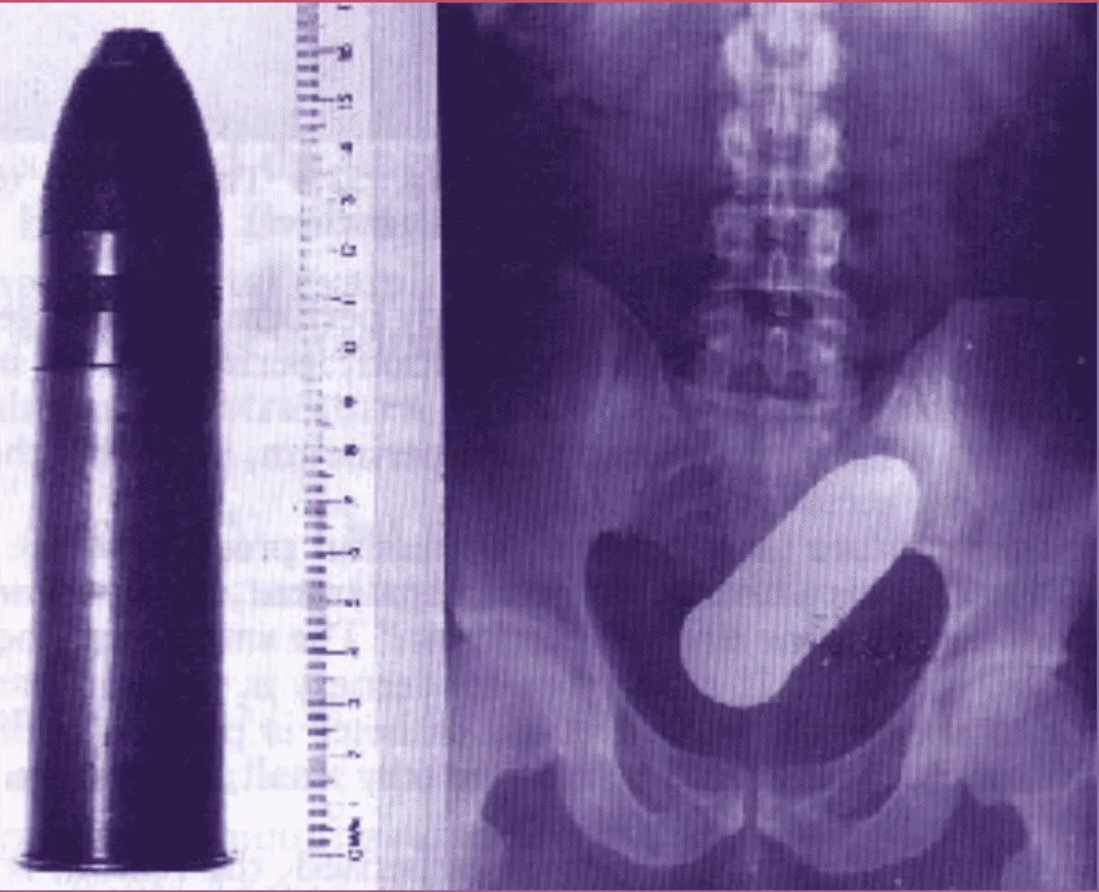

La scène a de quoi prêter à sourire, ou à grimacer : un jeune homme de 24 ans se présentant aux urgences de Toulouse avec un obus de 16 cm datant de 1918 dans le rectum. L’hôpital partiellement évacué